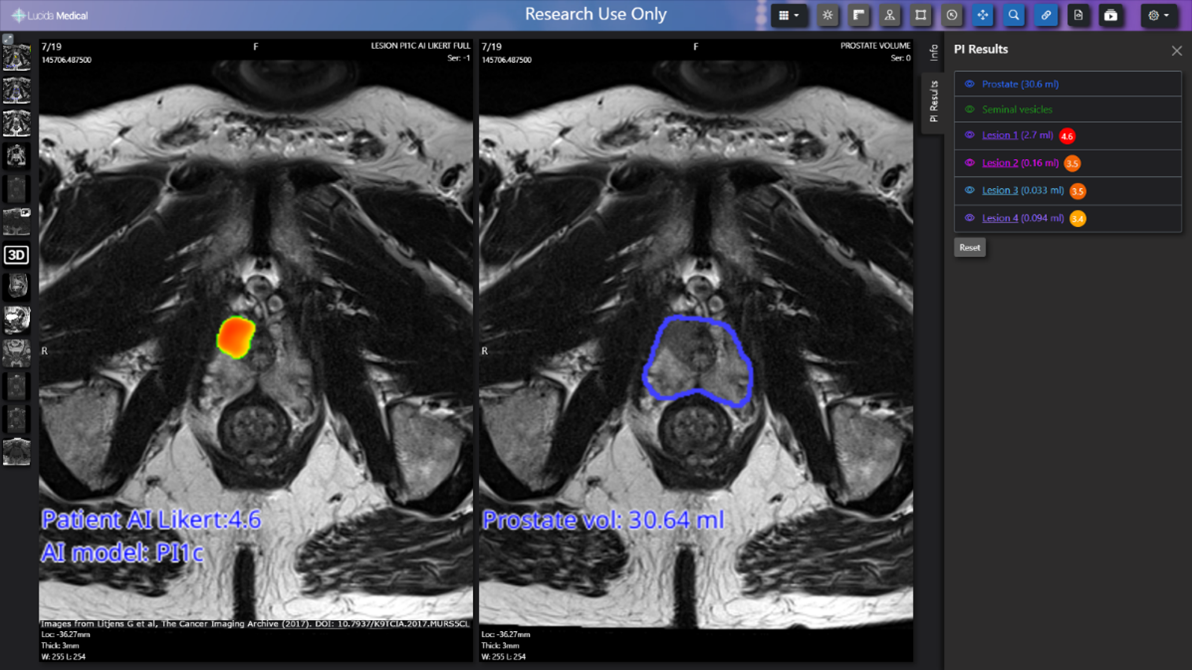

We have invested £350,100 in the pioneering new AI platform, Pi™, with the aim of improving the speed and accuracy of prostate cancer tests. Pi™, Prostate Intelligence™, is an AI and machine learning based software system designed to help radiologists detect and report the presence of prostate cancer lesions from MR scans (MRI). This could help to improve early detection and treatment and reduce the number of cancer-free patients going through more invasive investigative procedures, as well as potentially saving NHS time and money. The software has been developed by Lucida Medical.

Pi™ is built using Lucida Medical’s proprietary AI training technology that that has been trained to identify prostate cancer from MRI scans. Preliminary analysis suggests the software has accuracy comparable to expert radiologists, according to results presented at the 2023 International Cancer Imaging Society annual meeting from a diverse group of six NHS hospitals who are participating in the PAIR-1 clinical study [v]. Making the Pi™ software available to radiologists across the NHS could help speed up the work of radiologists and reduce the risk of both missing cancers and unnecessary biopsies.